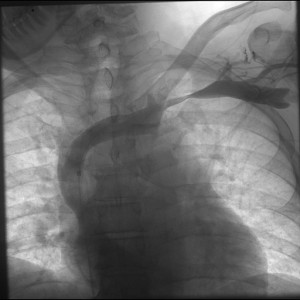

Venography is recommended in two instances. First, if the diagnosis is suspected, but proof was not obtained otherwise. For instance, when the duplex is inconclusive. The second use for venography, of course, is during a procedure. Venography often reveals venous collaterals, suggesting chronic sub-total compressions have been present. Furthermore, venography can be performed when the hand is in the neutral position or abducted. If extrinsic compression is visible, that suggests Paget Schroetter. Surprisingly CT and MR are not well suited imaging modalities for diagnosing Paget Schroetter, despite their obvious capabilities in diagnosing clot per se.

Thrombolysis

Several series show that early treatment with thrombolysis has better success rates than later treatment. Obviously, I mean local, catheter directed, thrombolysis. However, without complimentary treatment recurrence rates are high, as shown in a prospectively collected cohort treated by either thrombolysis and surgery or thrombolysis alone. In this cohort recurrence was especially high in young patients who did not have surgery (23%), while surgical treatment achieved a high long-term success rate (93%). However, there is another way to look at the same data. Many of the patients who received thrombolysis alone did well in the long-term.